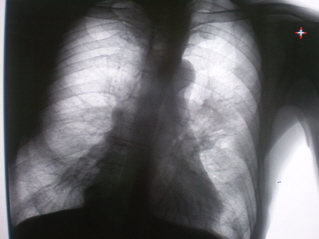

В 2007 году, находясь на стационарном лечении в терапевтическом отделении по поводу хронического бронхита, пневмосклероза был направлен на флюорографическое исследование органов грудной полости. На обзорной цифровой флюорограмме органов грудной полости, произведенной в прямой стандартной проекции с обеих сторон в базальных, преимущественно в медио – базальных отделах определяется усиление, обогащение и деформация легочного рисунка за счет явлений хронического бронхита и пневмосклероза. Имеет место некоторая деформация грудной клетки, сужение межреберных промежутков слева в верхних отделах. В грудном отделе позвоночника выраженные явления дистрофического характера в виде явлений межпозвонкового остеохондроза и деформирующего спондилеза. Определяется некоторое расширение тени левого корня, преимущественно в области тела, с некоторой гомогенизацией и потерей четкости наружного контура корня. В прикорневой области усиление и обогащение рисунка, преимущественно за счет линейных компонентов, направленных к периферии.

На иллюстрациях 1 и 2 – картина флюорографического изображения, с последующей оцифровкой изображения с применением эквилизации и увеличения. После исследования заподозрен рак левого лёгкого, с преимущественным «перибронхиальным ростом». Согласно «стандарту» произведено рентгенологическое дообследование пациента – прямая и левая боковая рентгенограммы; линейные томограммы в прямой проекции через левый – срезы 9, 10 11 см. После проведенного исследования был выставлен диагноз «Рак левого лёгкого, исходящий из корня, с преимущественным перибронхиальным ростом». Пациент консультирован в онкологическом диспансере. Было проведено дообследование, рекомендовано проведение противовоспалительного лечения. После проведения указанного лечения, при повторной консультации в онкологическом диспансере (в том числе с проведением рентгенографии) отмечена положительная динамика и выставлен диагноз хронического неспецифического воспалительного процесса.